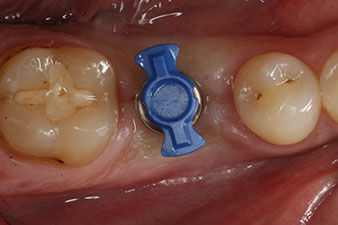

Nach Abheilung der Weichgewebe wurde vor der weiteren prothetischen Versorgung die Implantatstabilität erneut bestimmt.

Beide Werte waren praktisch unverändert und lagen im Übergang vom mittleren in den hohen Bereich – wobei der niedrigere Wert immer als therapiebestimmende Referenz dient.

Damit konnten eine erfolgreiche Osseointegration und ausreichende biologische Stabilität dokumentiert werden, die eine Abformung in derselben Sitzung erlaubte.